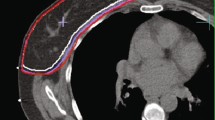

Fig. 1 supplementary material: A

dose distribution in a patient treated with PBI at the MRL. B dose distribution in a patient treated with PBI at the CTL. Structures depicted are: CTV, PTV, clips (yellow in A and blue in B), Seroma if present (in B), lungs and breasts ipsilateral and contralateral.